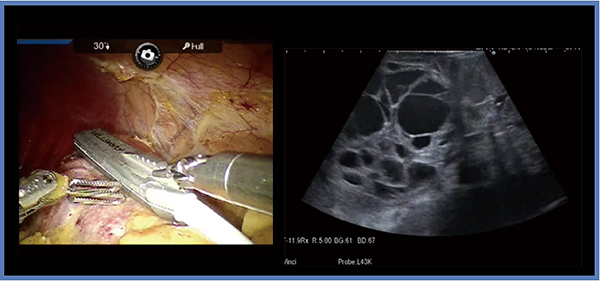

症例1は,74歳,男性,5.1cmの左腎細胞がんである(図2)。腫瘍が半分以上埋没しているため,なるべく少ないマージンで速やかに腫瘍底まで切除し,その後切り上げていく。その際,前述のとおり適切な切除ラインをイメージすることが重要であり,術中エコーがきわめて有用である。L43Kを腫瘍にしっかりと押し当てることで従来よりもかなり明瞭な画像が得られ(図2右),また,プローブ先端は小さくても腫瘍全体のイメージを十分につかむことができる。本症例は,阻血時間は26分とやや長めであるが,残すべき血流はしっかりと残し,不要な尿路の損傷を防ぐことで術後合併症もなく,腎機能も血清クレアチニン濃度(s-Cre)が術前0.93mg/dLに対し術後1.01mg/dLと十分に保たれていた。

図2 症例1:左腎細胞がん(74歳,男性)